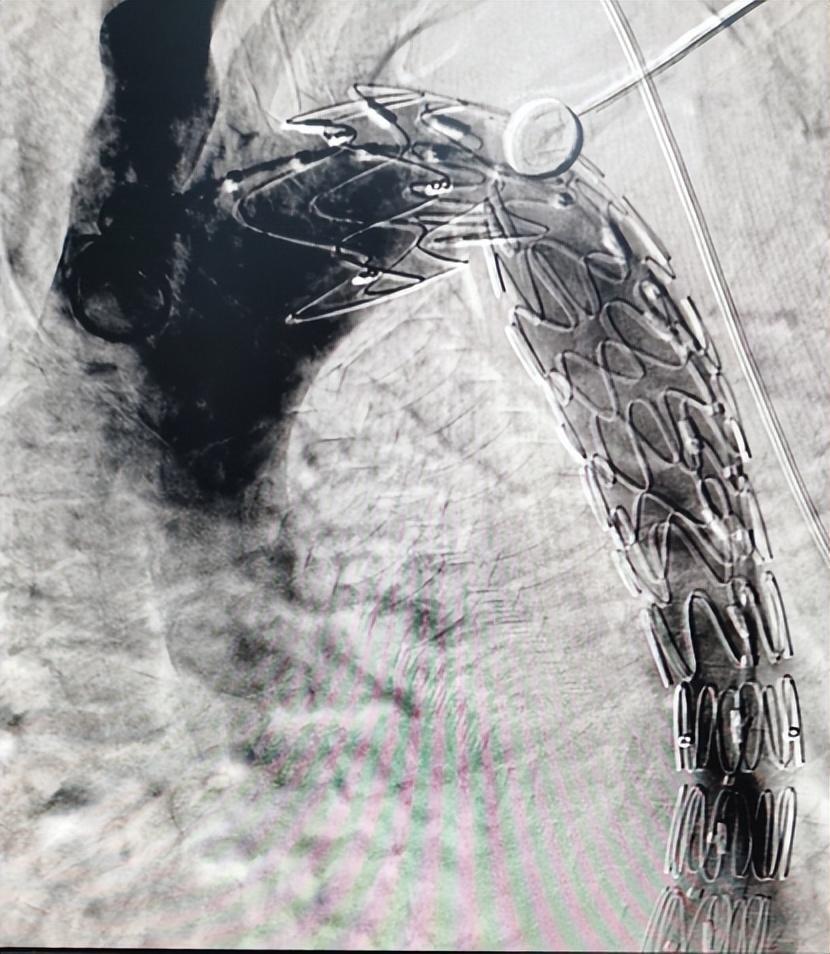

医院介入医学科团队应用castor分支支架成功救治一例胸主动脉夹层患者

图片尺寸750x410